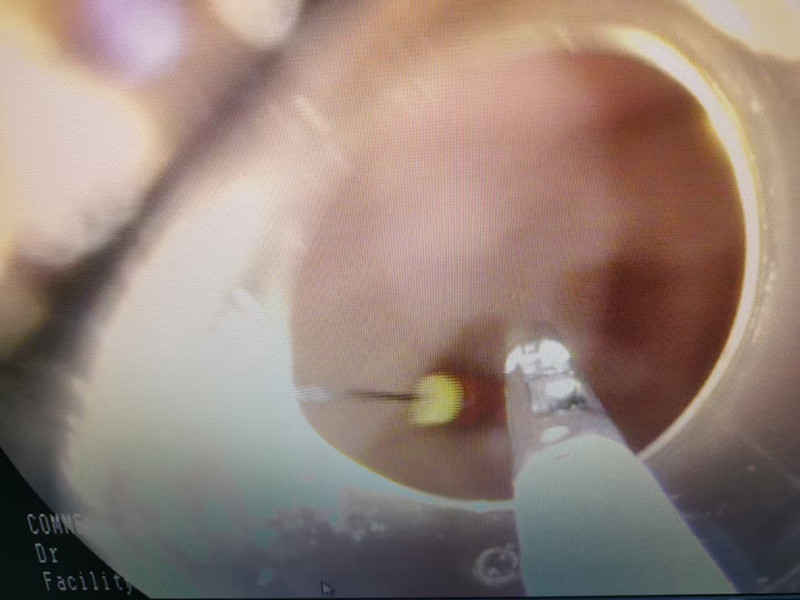

用一招,避免扎伤消化道图片

手术的危险之处在于修牙针针尖儿朝上,取针过程中稍有不慎,就会扎伤悠悠的消化道。

考虑到这一点,边鹏在内镜顶端套上硬质透明帽,钳取过程中,将针尖儿夹到透明帽里,有效避免了针尖儿损伤消化道的可能。

3分钟,取出4厘米修牙针图片

在手术团队成员的密切配合下,仅用3分钟,修牙针被成功取出,悠悠的消化道毫无损伤。经测量,悠悠吞的修牙针足有4厘米长。好在,悠悠就诊及时,医护人员手术及时,让悠悠转危为安。从悠悠入院到异物取出,仅40分钟。